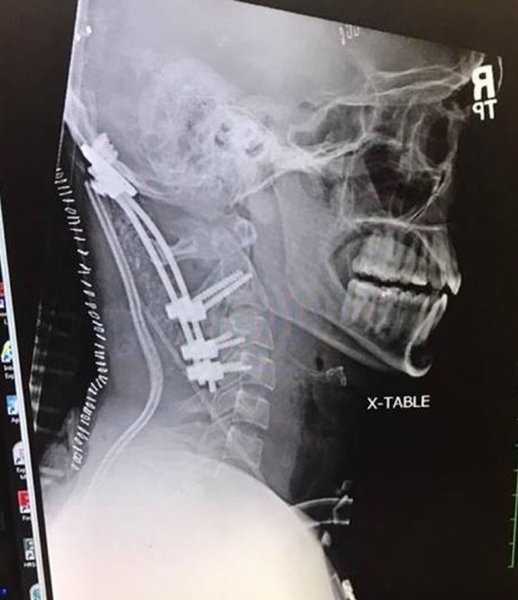

Врачи, приехавшие на место ДТП, констатировали "внутреннее обезглавливание". Это значит, что все связки, которые крепят череп к позвоночнику, порваны, а голова держится на одной коже.

Специалисты говорят, что с такой травмой не выживают, но Брок продолжал дышать. Хирурги провели сложнейшую операцию, закрепив в шее парня металлические штифты.